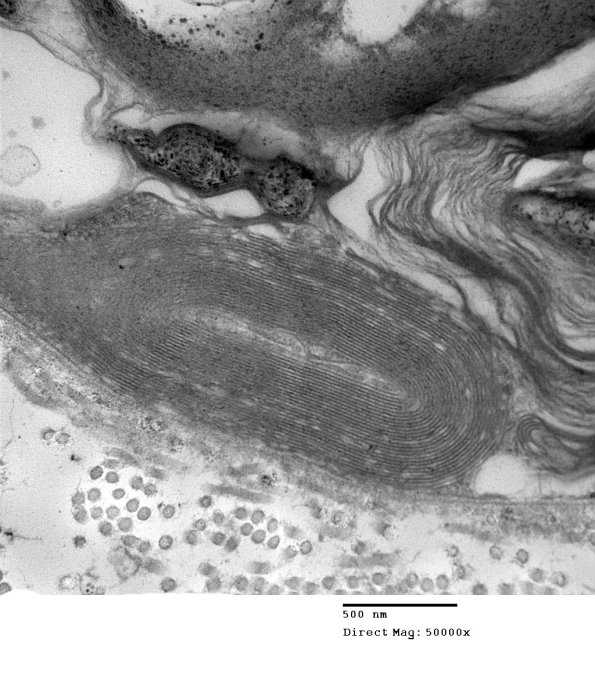

In many cases fragments of myelin may maintain their characteristic periodicity.